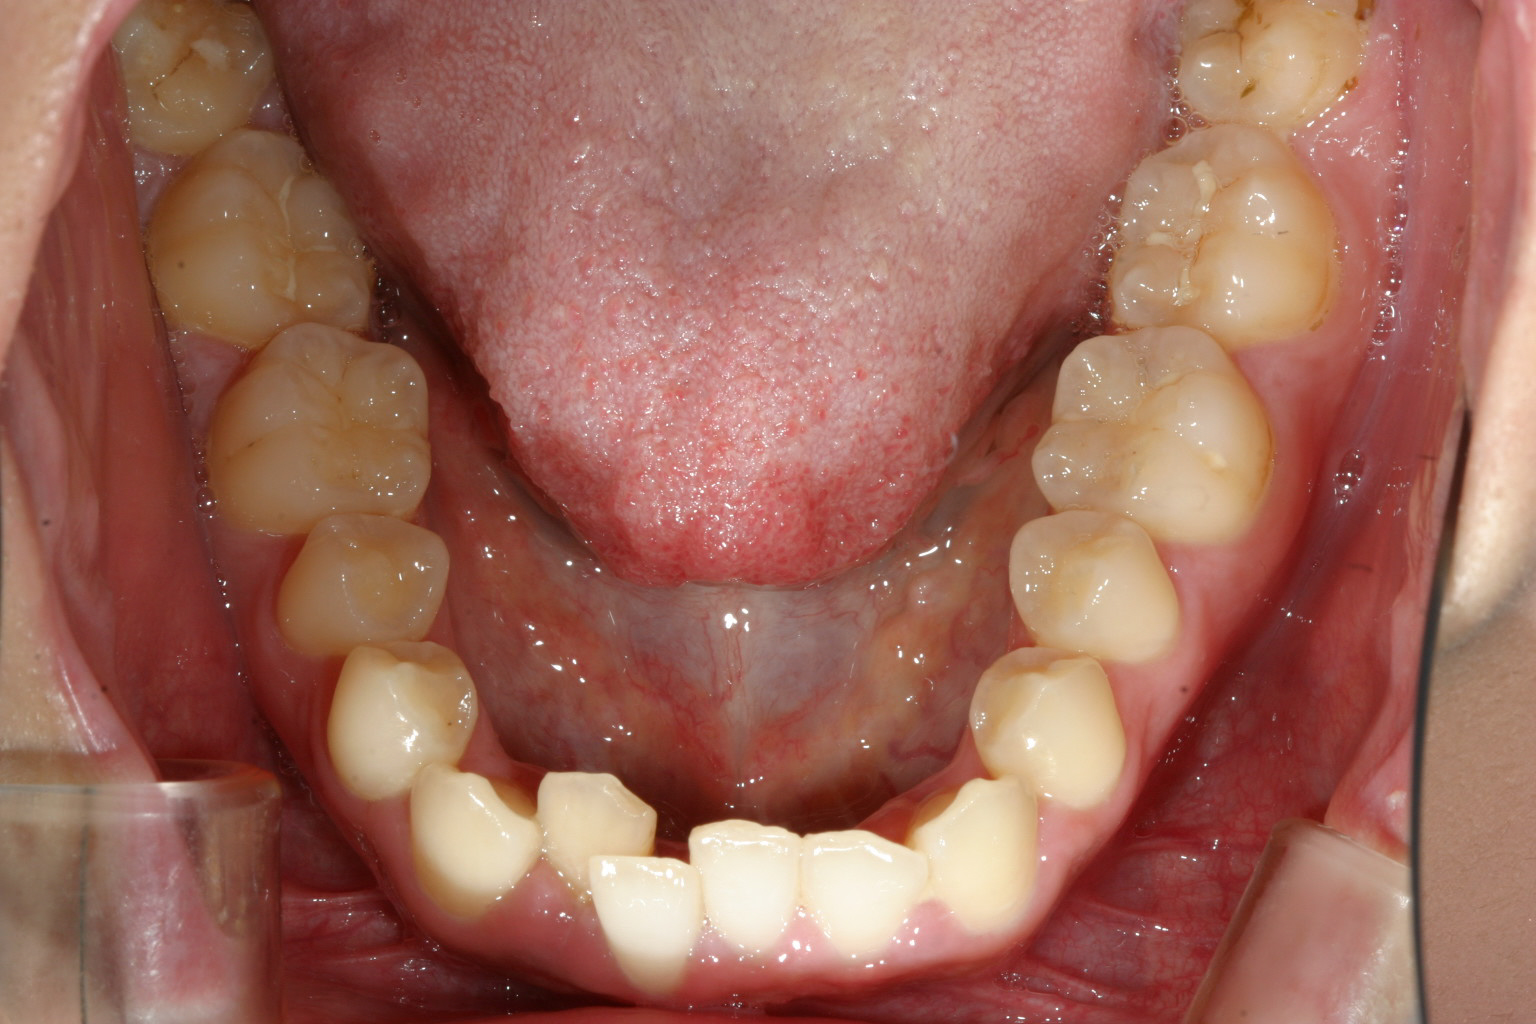

下顎もアーチが狭くV字型をしていて叢生が目立ちます。

横から見た感じは少し切端咬合気味です。